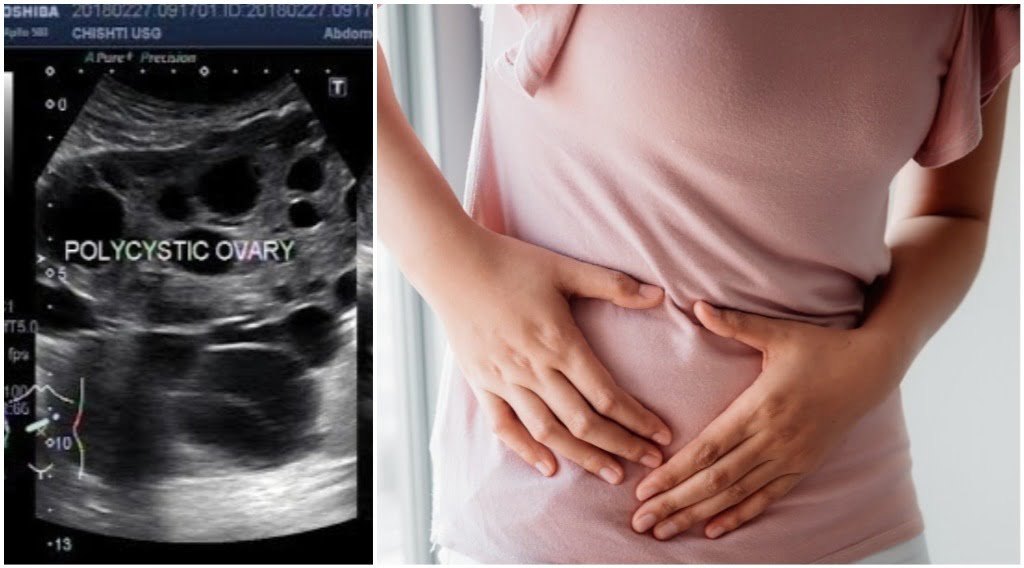

Polycystic Ovary Syndrome ( PCOS ) atau Sindrom Ovari Polisistik ialah satu keadaan hormon yang biasa berlaku dalam kalangan wanita usia subur . Dianggarkan bahawa lebih kurang 12.6% wanita di Malaysia menghidap PCOS . Yang mengejutkan , hingga 70% wanita dengan PCOS tidak tahu mereka menghidapnya . Kebanyakkan hanya sedar selepas berjumpa dengan doktor untuk masalah kesuburan atau haid yang tidak normal . PCOS berlaku apabila ovari menghasilkan hormon androgen ( hormon lelaki ) secara berlebihan . Ini akan mengganggu proses ovulasi dan menyebabkan pelbagai simptom lain .

● Pelvic Scan - Kehadiran sista kecil pada ovari